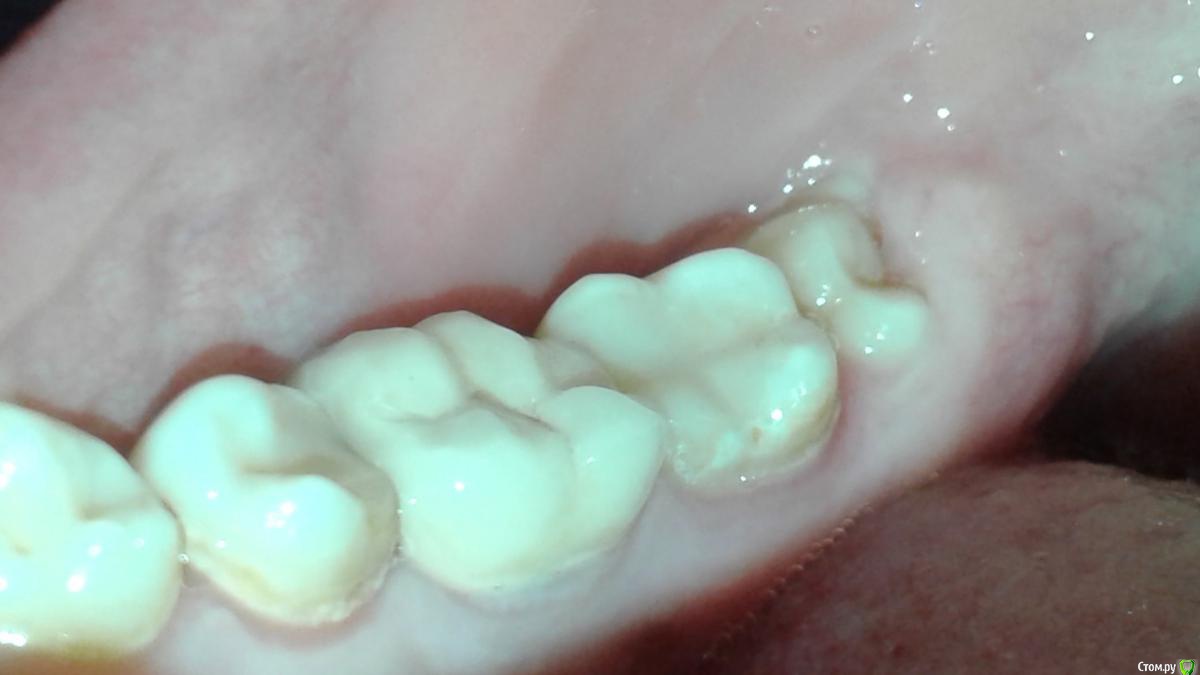

Инна2106 Опубликовано 27 июля, 2018 Поделиться Опубликовано 27 июля, 2018 (изменено) Добрый день.Прошу помочь определить в чем может быть причина ситуации с зубом которая длиться уже две недели.Началось все в ночь 13 августа проснулась от боли в одном участке нижней челюсти, именно не зубе, а челюсти, боль не острая, а тупая ноющая. Встала, походила все прошло. Весь день ничего не болело. В ночь все повторилось уже дважды просыпалась от боли, не определенного зуба, а низа левой челюсти. Для снятия боли достаточно было просто походить в течении 5 минут, все успокаивалось.На следующий день пошла к врачу, сделал снимок, осмотрел, сказал, что есть небольшая гранулема под шестым зубом под коронкой из-за не до конца запломбированного канала, но это как оказалось старая проблема, определялась еще на ортопанораме зимой. Но по его словам она не может давать такого рода болей. Ночью не спала вообще, четыре раза вставала от болей, причем стоило только принять горизонтальное положение и начиналась ноющая боль в нижней челюсти слева, и потом верхней челюсти слева. Суть в том что боли появлялись именно когда ложилась, не важно днем или ночью, пока ходишь, сидишь ничего не беспокоило. Снова поехала на прием к врачу, сделал много проб, и воздухом и нитью, подозревал трещину по снимку рядом в зубе под пломбой, но сказал нить не цепляется и не рвется значит ее нет, но вскрывать этот зуб не смысла так как на простукивание все было спокойно и сверху и снизу. Десна все розовые, кровоточивости нет. Через три дня поехала к другому врачу сделал свой снимок, предположил как вариант что восьмерка может двигать зубной ряд оттуда и боль, но сама восьмерка абсолютно спокойна, не болит, нет отечности десны. Его заключение, что причина в троичном нерве, а не в зубах. До этого по рекомендации первого врача принимала Азитромицин 3 дня и Нимесил не помогло. Начала пить Нейродикловит (диклофенак с витаминами группы В) и наконец-то начала ночью спать, но с понедельника 23 июля начал болеть зуб при накусывании рядом с коронкой (семерка), я на эту сторону и так не ем уже две недели, почувствовала боль при пережевывании пищи. когда верхних зуб попадал на нижний, попробовала постучать ложкой и ощутила боль в семерке снизу. В среду поехала к третьему врачу, он сделал пришлифовку семерки нижней с верхней так как нагрузка на зуб неправильно распределялась на одно сторону, порекомендовал попить Нимесил и наблюдать.Суть в том, что на данный момент исчезли боли в горизонтальном положении, но не могу жевать и есть нормально, сам зуб не болит, но если попробовать накусить слегка зубочистку на семерку появляется боль, отпускаешь проходит.Очень прошу помогите разобраться что это и как себе помочь, скоро нужно уезжать и не знаю стоит ли сейчас снимать коронку или все же причина не в этом зубе. Стоит ли делать КТ, новую ортопанораму, если по снимкам ничего не видят. Внизу прикрепила фрагмент ортопанорамы делала в феврале этого года, и нашла снимок этого сделанный в конце апреля прошлого года для сравнения.Заранее большое спасибо. Изменено 27 июля, 2018 пользователем Инна2106 Ссылка на комментарий

red_butler Опубликовано 27 июля, 2018 Поделиться Опубликовано 27 июля, 2018 Да банально пульпит нижней семерки. Там кариес под пломбой, видно же. тут кандидатов на пульпит прорва 2 Ссылка на комментарий